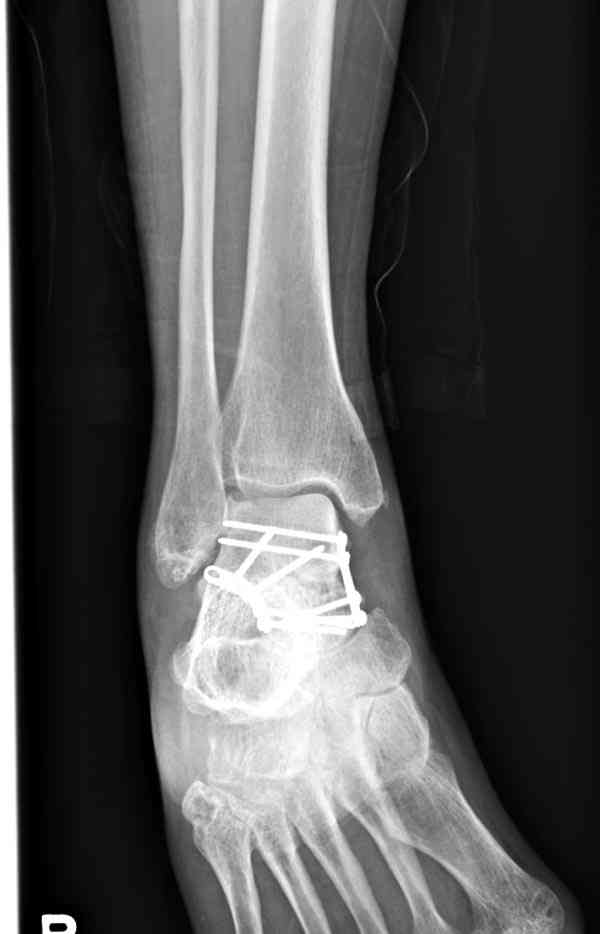

Случай с множественным оскольчатым переломом тарана оперированный из двойного доступа.

Через 2 мес.:

Через 8 мес.:

Через 14 мес.:

Два фрагмента суставной поверхности тарана можно восстановить боковой компрессией шурупами и дополнительно костная пластика.

(кстати, на нашем случае была применена костная пластика-allograft crouton для заполнения дефектов)

Наружный фиксатор "голень-пятка", "лигаментотаксис" при поступлении, домой через 48 часов после обучения ходьбы на костылях, в течение ближайшего времени осмотр в поликлинике для определения кондиции мягких ткани (тест на образование морщин в зоне разреза), при отсутствии отека примерно на 6-7 день с момента травмы операция.

Нагрузку можно разрешить через 2,5 месяца, на конечность снимаемый брейс удобен для разработки сустава которую можно начать после первичной перевязки.

Это примерная тактика при лечении переломов тарана.